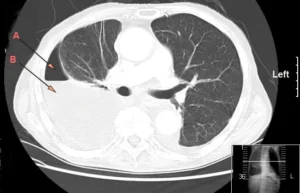

• Tomografia Computerizzata (TC) del Torace: In caso di sospetto empiema, la tomografia computerizzata può essere utile per ottenere immagini dettagliate della cavità toracica. La TC aiuta a valutare l’estensione dell’infezione, la presenza di complicazioni come la formazione di ascessi o fistole pleuriche e può guidare il trattamento terapeutico. È particolarmente utile per identificare empiemi complessi, come quelli con setti settici o empiemi saccati.

• Radiografia del torace: La radiografia del torace in due proiezioni (frontale e laterale) è spesso il primo passo diagnostico. Può mostrare segni di versamento pleurico, che è tipico dell’empiema. Tuttavia, una radiografia da sola non è sufficiente a confermare la presenza di pus o a determinare la gravità della condizione.